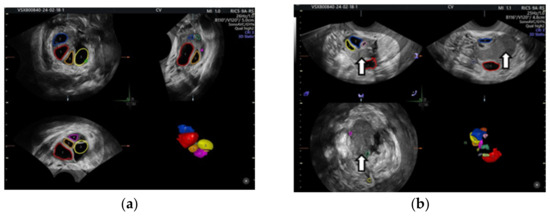

- Cohen Ben-Meir, L.; Mashiach, R.; Eisenberg, V.H. External Validation of the IOTA Classification in Women with Ovarian Masses Suspected to Be Endometrioma. J. Clin. Med. 2021, 10, 2971. [Google Scholar] [CrossRef] [PubMed] [PubMed Central]

- Guerriero, S.; Alcazar, J.L.; Ajossa, S.; Pilloni, M.; Melis, G.B. Three-dimensional sonographic characteristics of deep endometriosis. J. Ultrasound Med. 2009, 28, 1061–1066. [Google Scholar] [CrossRef] [PubMed]